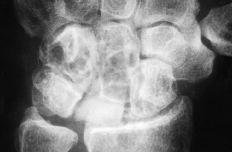

Figura 4. Radiografía posteroanterior de muñeca donde se muestra una luxación cubital del implante junto con un colapso carpiano y una traslación cubital.

Hubo dos luxaciones del implante hacia cubital, subluxación en otros dos, una palmar y otra dorsal, y presencia de DISI en seis y de VISI en dos. La siliconitis e imágenes líticas intraóseas (de predominio hueso grande-ganchoso) se dieron en ocho pacientes y la artropatía degenerativa radiocarpiana e intercarpiana en 10. Se realizaron reintervenciones en cuatro pacientes: tres artrodesis del carpo y una resección de la primera fila.